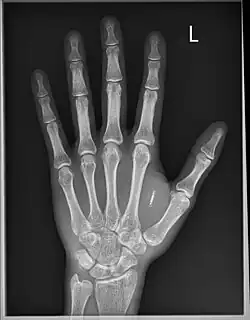

![]() Dangerous Things RFID implant in patient | |

Dangerous Things[1] is a Seattle-based cybernetic microchip biohacking implant retailer formed in 2013 by Amal Graafstra,[2] following a crowdfunding campaign.[3]

Dangerous Things built the first personal publicly available implantable NFC compliant transponder in 2013.[4] In September 2020, Dangerous Things began another highly successful crowdfunding campaign to realize the world's first titanium encased fully bio-compatible sensing magnet, named the Titan.